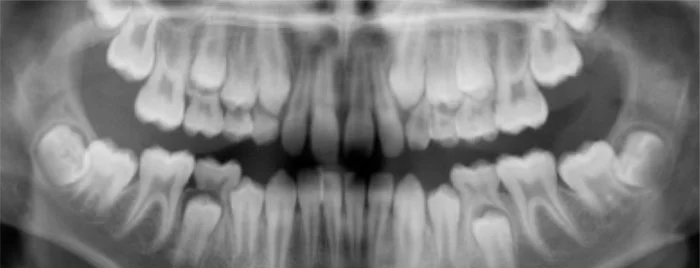

This panoramic x-ray shows baby teeth as well as the developing permanent teeth that have not yet reached the surface.